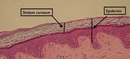

Diş eti yaraları, diş etlerinde meydana gelen iltihaplanma, enfeksiyon veya yaralanma sonucu oluşan rahatsız edici durumlardır. Bu yaralar, genellikle diş eti hastalıkları, travmalar veya ağız hijyeninin yetersizliği nedeniyle ortaya çıkar. Diş eti yaralarının etkili bir şekilde tedavi edilmesi, ağız sağlığının korunması açısından son derece önemlidir. Bu makalede, diş eti yaralarına iyi gelen yöntemler ve önleyici tedbirler ele alınacaktır. Diş Eti Yaralarının Belirtileri Diş eti yaraları genellikle aşağıdaki belirtilerle kendini gösterir: